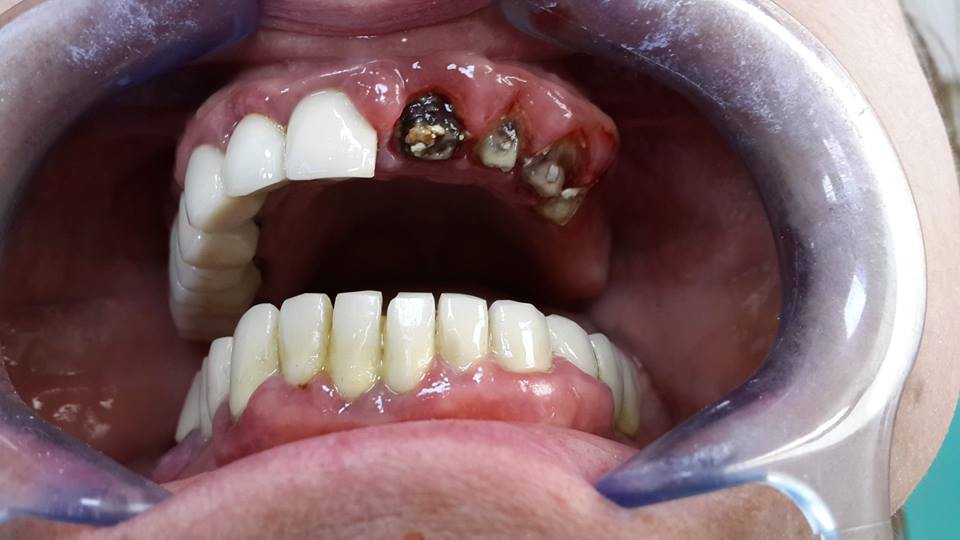

An example of complete rehabilitation of the oral cavity. Treatment included the removal of the old prosthesis, treatment of paradontitis, removal of a large cyst, implantation, clasp prosthesis.